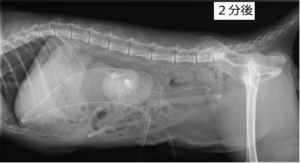

術後数日後に排泄性尿路造影した写真です。左右に2.1Frの尿管ステントと腹腔内に透析用のチューブが留置されています。